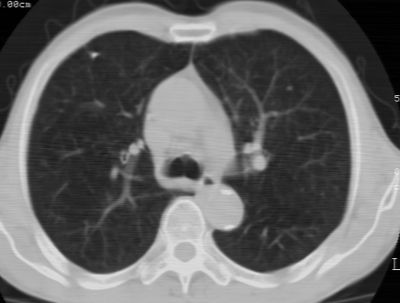

1、左肺上叶spn,毛刺+分叶+血管集束征,考虑周围型肺癌可能性大

2、全小叶性肺气肿。

1)左肺上叶周围型肺癌可能。2)两肺全小叶型肺气肿。

左上周围型肺癌,全小叶型肺气肿。